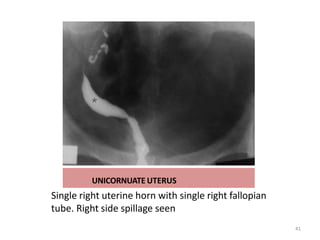

UNICORNUATE UTERUS

Single right uterine horn with single right fallopian

tube. Right side spillage seen